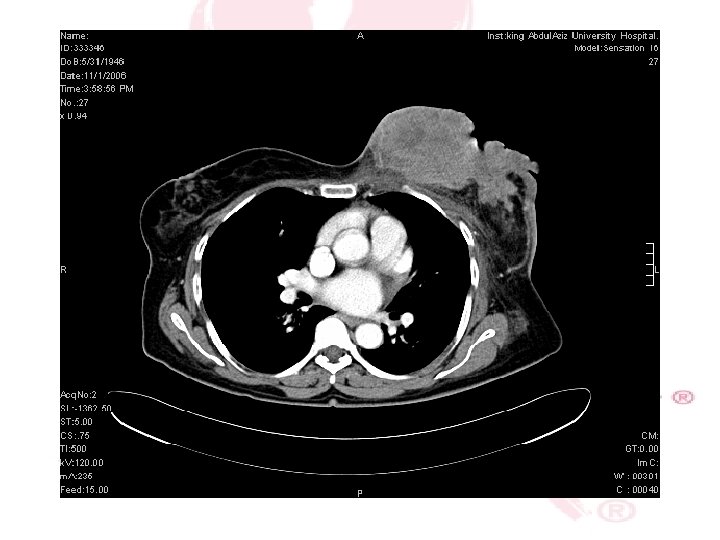

CT SCAN CHEST , ABDOMEN &PELVIS